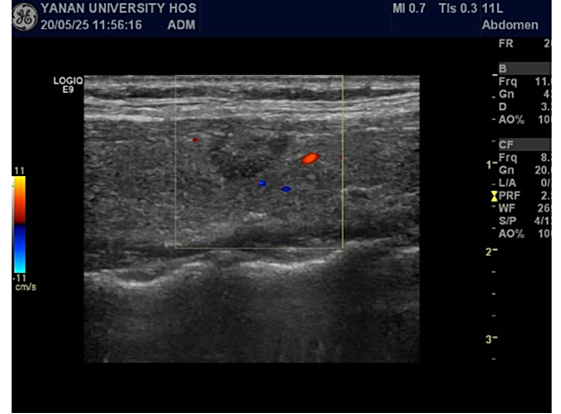

手术在超声医学科介入诊疗室完成。为了防止出现颈总动脉及喉返神经等重要组织损伤,我们在甲状腺周围注入生理盐水建立了隔离带,微波针进入病灶20s完成结节的消融。术后及时进行超声造影评估,甲状腺结节完全消失。

术后甲状腺结节情况